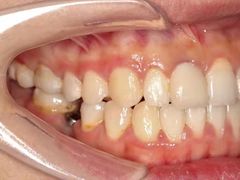

• -联合口腔(西环诊所)

在丽江古城跳舞的炒鸡蛋 | 21-05-08

报错